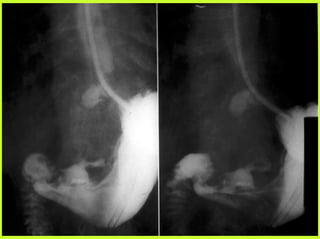

PERITONITE PAR PERFORATION

D’ULCERE DUODENAL (2)

TRAITEMENT

1 NON CHIRURGICAL DANS CERTAINES

CONDITIONS

- aspiration (méthode de TAYLOR)

- à distance d’un repas

- moins de 6 heures après la perforation

- surveillance en milieu chirurgical

- poursuivi si après 6 heures : $ $ des SF

- AB, réanimation IV, diète stricte

2 CHIRURGICAL (coelio ou laparo)

- suture de la perforation

- parfois traitement radical de l’ulcère : vagotomie

ou gastrectomie

D’ULCERE DUODENAL (1)

Ulcère de la face ANTERIEURE du bulbe (9/10)

- Douleur à début horaire, épigastrique

- Douleur provoquée, défense voire contracture

hypochondre droit, flanc droit, FID

- Peu ou pas de vomissement

- Pas d’hyperthermie (12 premières heures)

- Pneumopéritoine clinique et/ou RADIO (50%)